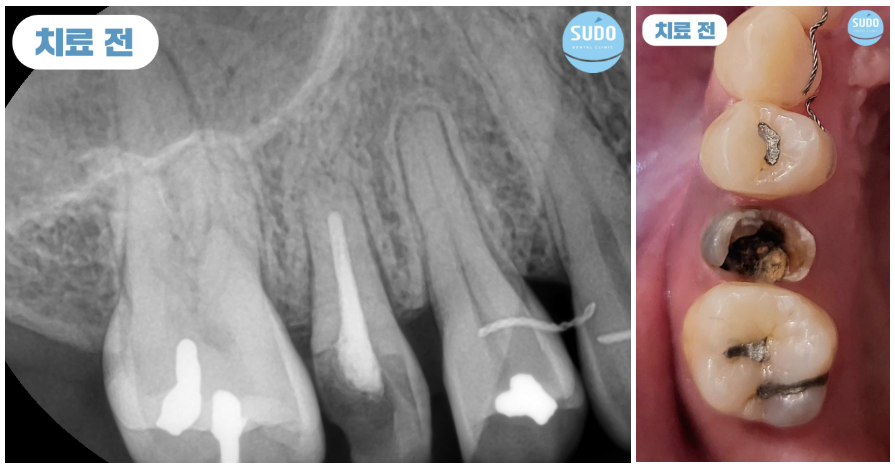

그 부분만을 확대하여 x-ray 사진 촬영해 본 결과 치아 뿌리 안쪽까지 심한 충치로 인해 발치 후 임플란트를 진행하셔야 하는 상태였습니다. 임플란트 경험이 없으셨던 환자분을 위해 수도치과 의료진들의 충분한 치료 설명을 통해 발치 후 부산영도임플란트 식립 계획을 수립하였습니다.

처음 내원하셨을 때는 외국 거주 중이셨고, 열흘 후에 출국 예정이셨습니다. 이에 따라 내원 당일에 발치 후 즉시 임플란트를 식립하셨고, 주변 치아의 이동을 예방하기 위해 유지 철사를 부착한 후 다시 출국하셨습니다.